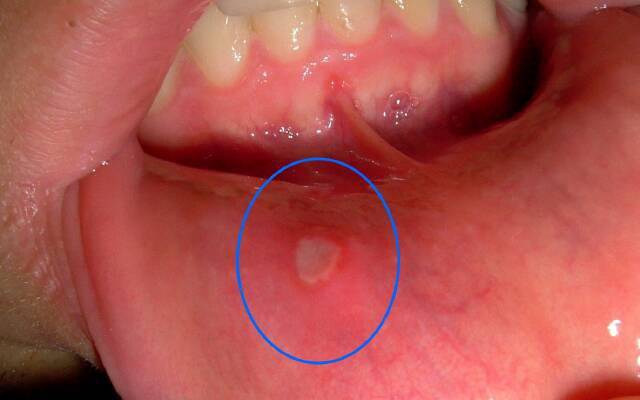

афтозний

У дорослих проявляється утворенням невеликих ранок круглої форми - афт, що мають білий або жовтуватий відтінок з червоною окантовкою. Іноді виникає при механічних пошкодженнях передньої частини ротової порожнини: на губах, щоках, кінчику язика. Більшість медиків схиляються на думці, що етимологія афтозного стоматиту вірусна, називаючи причинами аденовіруси, герпетическую інфекцію.

Хронічний перебіг захворювання у дорослих з частими рецидивами свідчить про наявність захворювань шлунково-кишкового тракту або печінки. Виявляється такими симптомами: множинні ураження губ, щік, мови; хворобливі відчуття, що заважають прийому їжі; підвищення температури тіла до 38. Лікування стоматиту будинку включає комплекс заходів, пов'язаних із симптоматичними ознаками, зміцненням імунітету.